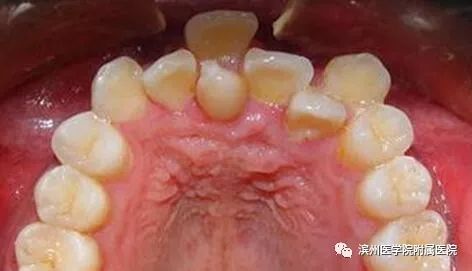

李奶奶的宝贝孙子6岁半了,上颌前面的两颗门牙已经替换了三个多月,可是两颗新牙间缝隙不见变小,反而越来越大了,远没有乳牙长得那么整齐。孙子门牙有大缝这事最近让李奶奶一直着急上火,平日总挂在脸上的笑容也不见了,今天一大早就带着孩子到滨州医学院附属医院儿童口腔科检查。儿童口腔科的医生经过专科查体并配合X线检查,发现是孩子的两颗新长门牙之间有一颗多生牙在作怪。